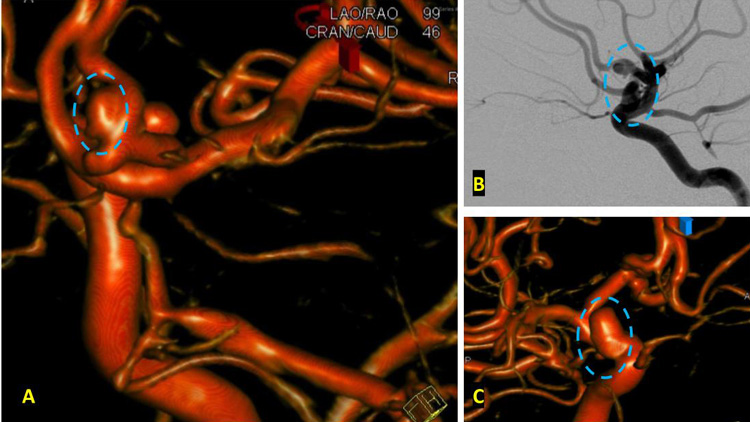

On admission, she presented as a GCS 3, was intubated, and stabilized hemodynamically in preparation for emergent catheter cerebral angiography, which revealed 2 discrete geographically located aneurysms – 1) Anterior Communicating and 2) Right ICA Supra-Clinoid Segment. (Figure 2.)

After careful measurements of the parent vessels, aneurysm sac, and aneurysm neck, we decided to proceed with Primary Coil Embolization of the Acom Aneurysm first, followed by the Right ICA Aneurysm next. Despite greater suspicion in the Acom region, a significant level of uncertainty remained, and we felt it was better to secure both aneurysms if capable of being performed safely. (Figure 4.)